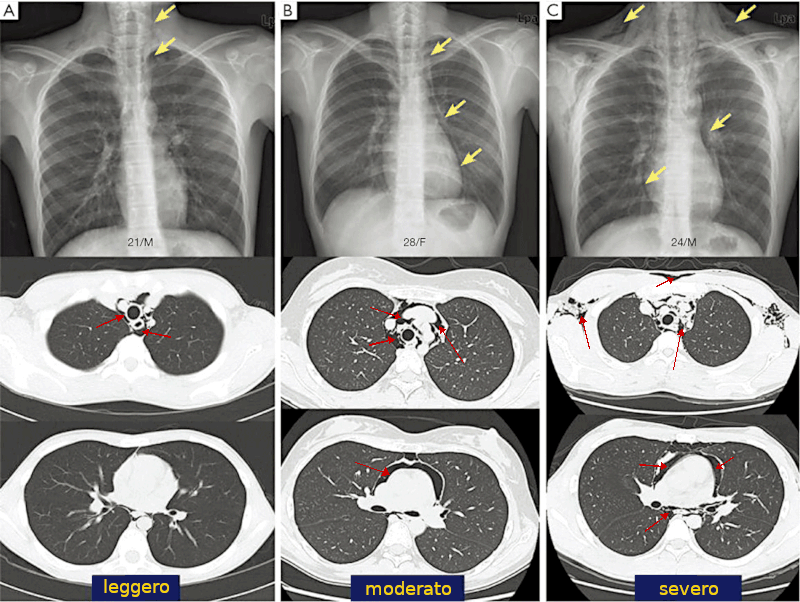

Immagini non riferite al caso in descrizione